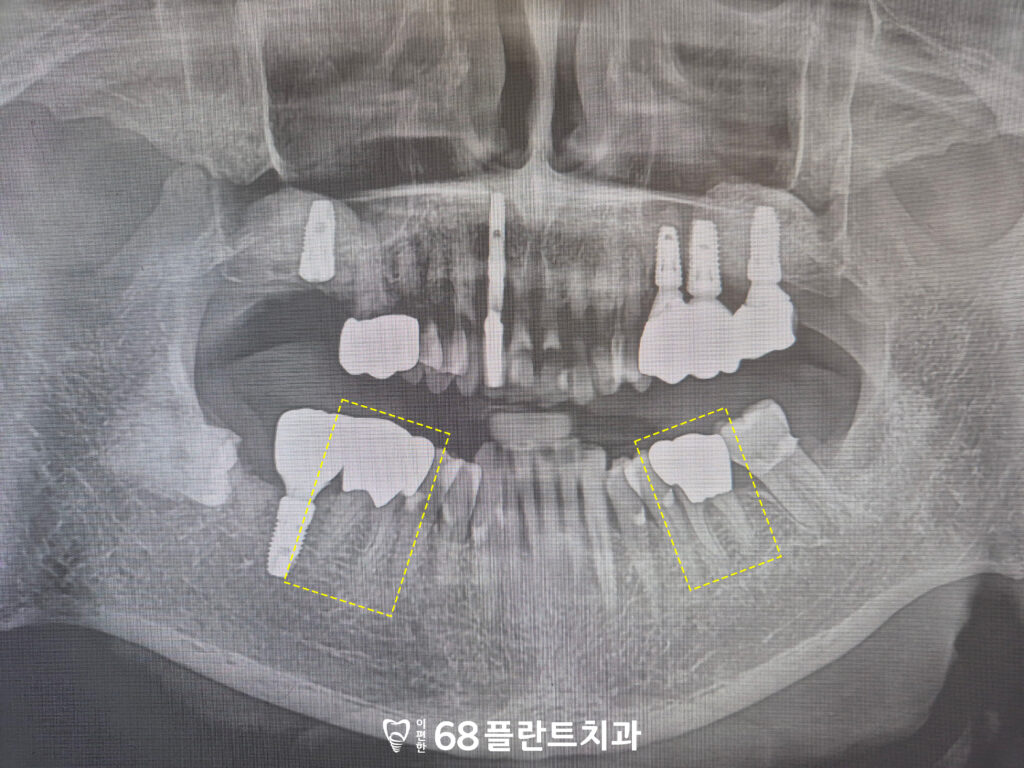

19.11.20

위 환자분은

씹을 때마다 치아가 불편하고

상실된 부위도 있어

전체적으로 식사하기 힘들다며

철산역치과 이편한68플란트에

내원해 주셨습니다.

확인해 보니,

치아가 마모가 되어있는 부위도 있었으며

뿌리 끝 염증이 생겨있는 것도

확인할 수 있었습니다.

또한 위쪽 끝 어금니가 상실되어 있어,

오랜 기간 동안 씹는 힘의 균형이 무너지다 보니

맞닿는 아래쪽 어금니가 서서히

위 방향으로 솟아오르는 정출 현상까지

진행된 상태였습니다.

그래서 해당 부위들은 발치 진행 후

임플란트를 식립 하기로 하였습니다.

또한 치아가 상실되었던 부위는

잇몸뼈의 흡수로 인해 공간이 부족하여

상악동거상술을 함께

진행하기로 하였습니다.